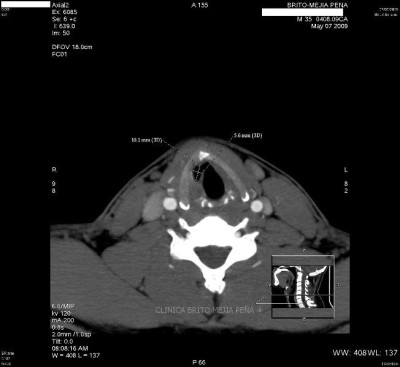

Divertículo traqueal axial

Divertículo traqueal aire